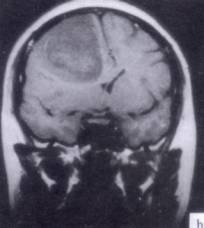

病历摘要:??患者男性,52岁。头痛伴呕吐2月,呕吐呈喷射性。既往身体健康。体检:神清,表情淡漠,反应迟钝,双眼底视神经乳头明显水肿,左鼻唇沟稍浅,左腹壁...

问题 病历摘要:??患者男性,52岁。头痛伴呕吐2月,呕吐呈喷射性。既往身体健康。体检:神清,表情淡漠,反应迟钝,双眼底视神经乳头明显水肿,左鼻唇沟稍浅,左腹壁反射减弱,左上下肢肌力4级,左Babinski征(-)。 术前的检查和治疗应包括下列哪些??提示:初步诊断考虑胶质瘤,拟手术治疗